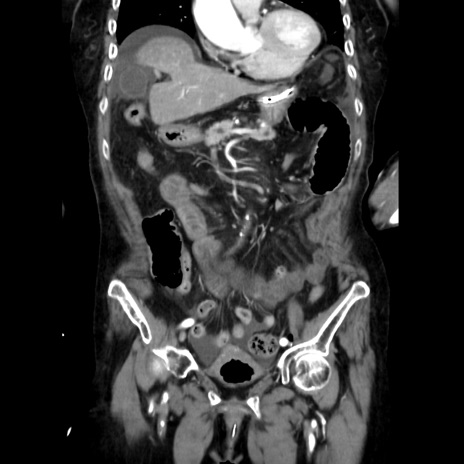

症例40(冠状断像)

【症例】90歳代女性

【主訴】腹痛・嘔吐

【現病歴】 食欲低下、嘔吐があり昨日他院受診。肺炎と診断され入院となる。入院後より腹部全体に圧痛あり。胃管留置され経過みていたが、症状持続するため、

当院転院となる。

【身体所見】腹部:中央に激痛あり、圧痛あり、反跳痛不明

【データ】WBC 17100、CRP 18.82

冠状断像